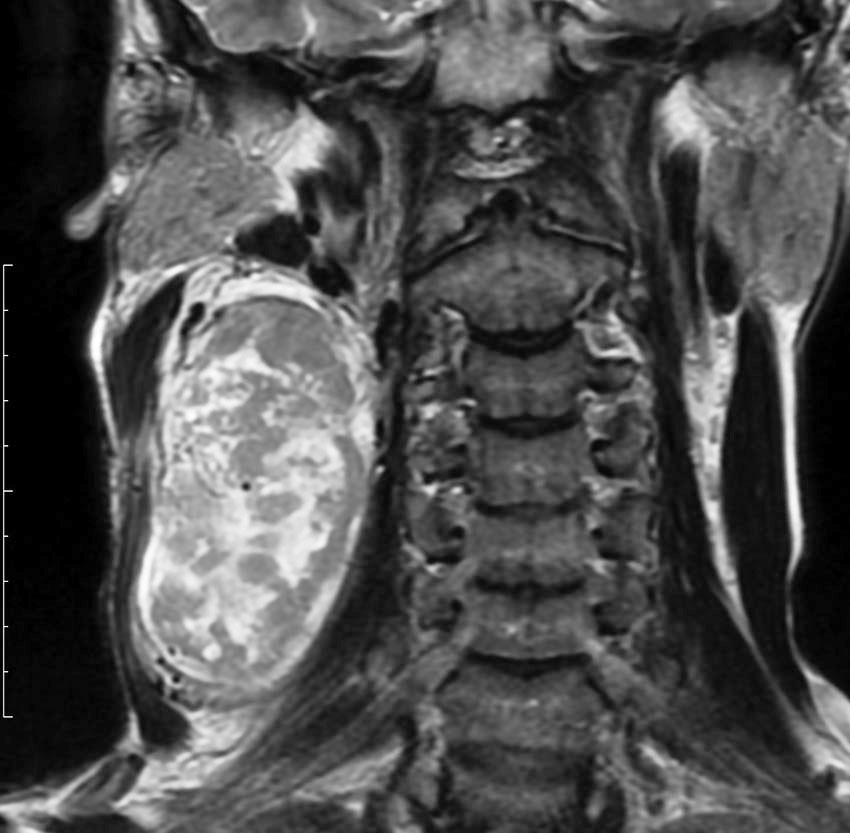

10歳くらいから頸部に腫瘍があり生検術をされましたが診断がつかず,31歳までなにも治療をしなかった患者さんです。20年間でかなりゆっくり大きくなりました。

30代で,血行性肺転移が多発しているという診断を受けました。20年以上の病歴があり,多くの血管に富むhypervascular tumorであったために,良性腫瘍であるパラガングリオーマの肺転移という術前診断で頸部腫瘍の摘出をしました。

全摘出して術後経過に問題はありませんでしたが,病理診断は,全体がリンパ球と胚中心様の構造でCastleman diseaseでした。発熱や倦怠感などの症状がなく軽症の単中心性キャッスルマン病として経過したものかもしれません。